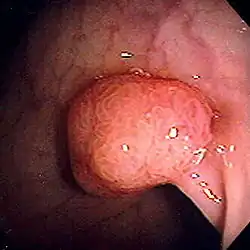

Polip jest pojęciem makroskopowym, odnoszącym się do rozrostów łagodnych błon śluzowych. W typowej postaci ma on kształt maczugowaty, składa się z cienkiej nóżki (szypuły), zawierającej wiązkę naczyń odżywiających oraz kulistego, miękkiego zgrubienia. Nazwa była pierwotnie używana wobec szczególnej postaci przewlekłego zapalenia wytwórczego błon śluzowych, w których dochodzi do rozrostu tkanki łącznej włóknistej blaszki właściwej błon śluzowych (łac. inflammatio chronica proliferativa polyposa). Obecnie pojęcie to jest używane także jako określenie makroskopowe niektórych nowotworów łagodnych (gruczolaków polipowatych – łac. adenoma polyposum), jak również zaburzeń rozwojowych mających kształt polipa.

Polipy uszypułowane (posiadające rodzaj „nóżki”) jest stosunkowo łatwo usunąć w trakcie badania endoskopowego przy pomocy pętli, natomiast polipy o szerokiej podstawie zwykle są przed usunięciem obstrzykiwane. Badanie endoskopowe, wyskrobiny są najczęstszymi zabiegami diagnostycznymi mającymi na celu pozyskanie tkanek polipa celem ustalenia jego postaci i etiologii przy pomocy badania mikroskopowego. Należy dążyć do tego aby podczas biopsji usunąć możliwie jak największą masę polipa, a zwłaszcza jego szypułę. W przypadku polipów nowotworowych, jeśli w obrębie jego szypuły znajdowany jest naciek raka, niezbędne bywa szybkie poszerzenie zabiegu (wycięcie danego narządu w granicach zdrowych tkanek).